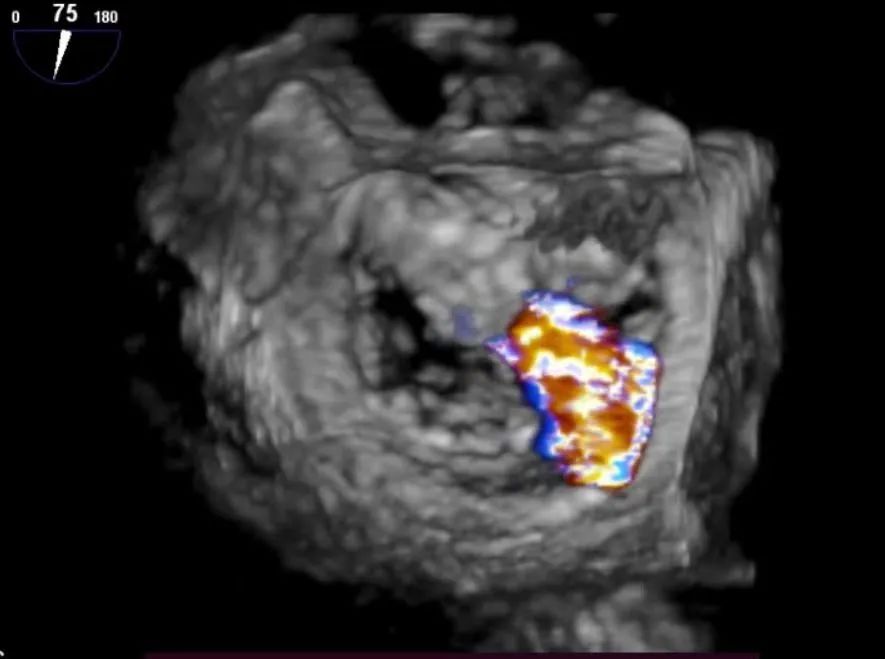

术前xPlane view提示:二尖瓣重度反流

术后xPlane view提示:二尖瓣反流显著减少

术前3D view提示:二尖瓣重度反流

术后3D view提示:二尖瓣反流显著减少